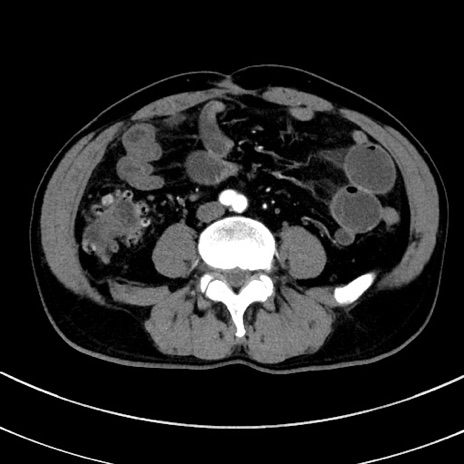

症例8(横断像)

【症例】 60歳代男性

【主訴】 黒色吐物

【現病歴】 4日前から嘔気自覚、2日前の朝食後にも嘔気あり、自分で手で嘔吐反射起こし嘔吐したところ血が混ざっていたため受診。

【既往歴】 5年前汎発性腹膜炎を伴う急性虫垂炎で手術、高血圧、前立腺肥大症、高脂血症

【身体所見】 腹部正中に手術癩痕あり 腹部平坦・軟圧痛なし膨満感あり

【データ】WBC 8400、CRP 4.54